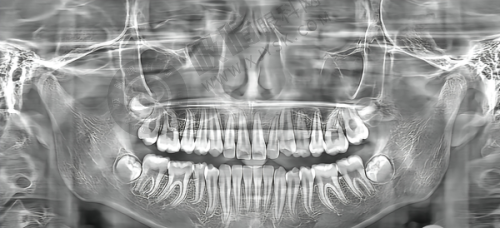

种植牙是特别多牙齿缺失患者的优选修复方式,武汉大学中南医院口腔科提供多种品牌的种植牙供患者选择,价格区间也比较广泛。

不同品牌种植牙因材质、性能等不同,价格有所差异。患者可以根据自己的口腔情况和经济实力来选择适合自己的种植牙品牌。

半口种植牙价格 40000 - 60000 元起,全口种植牙价格 100000 - 110000 元起。